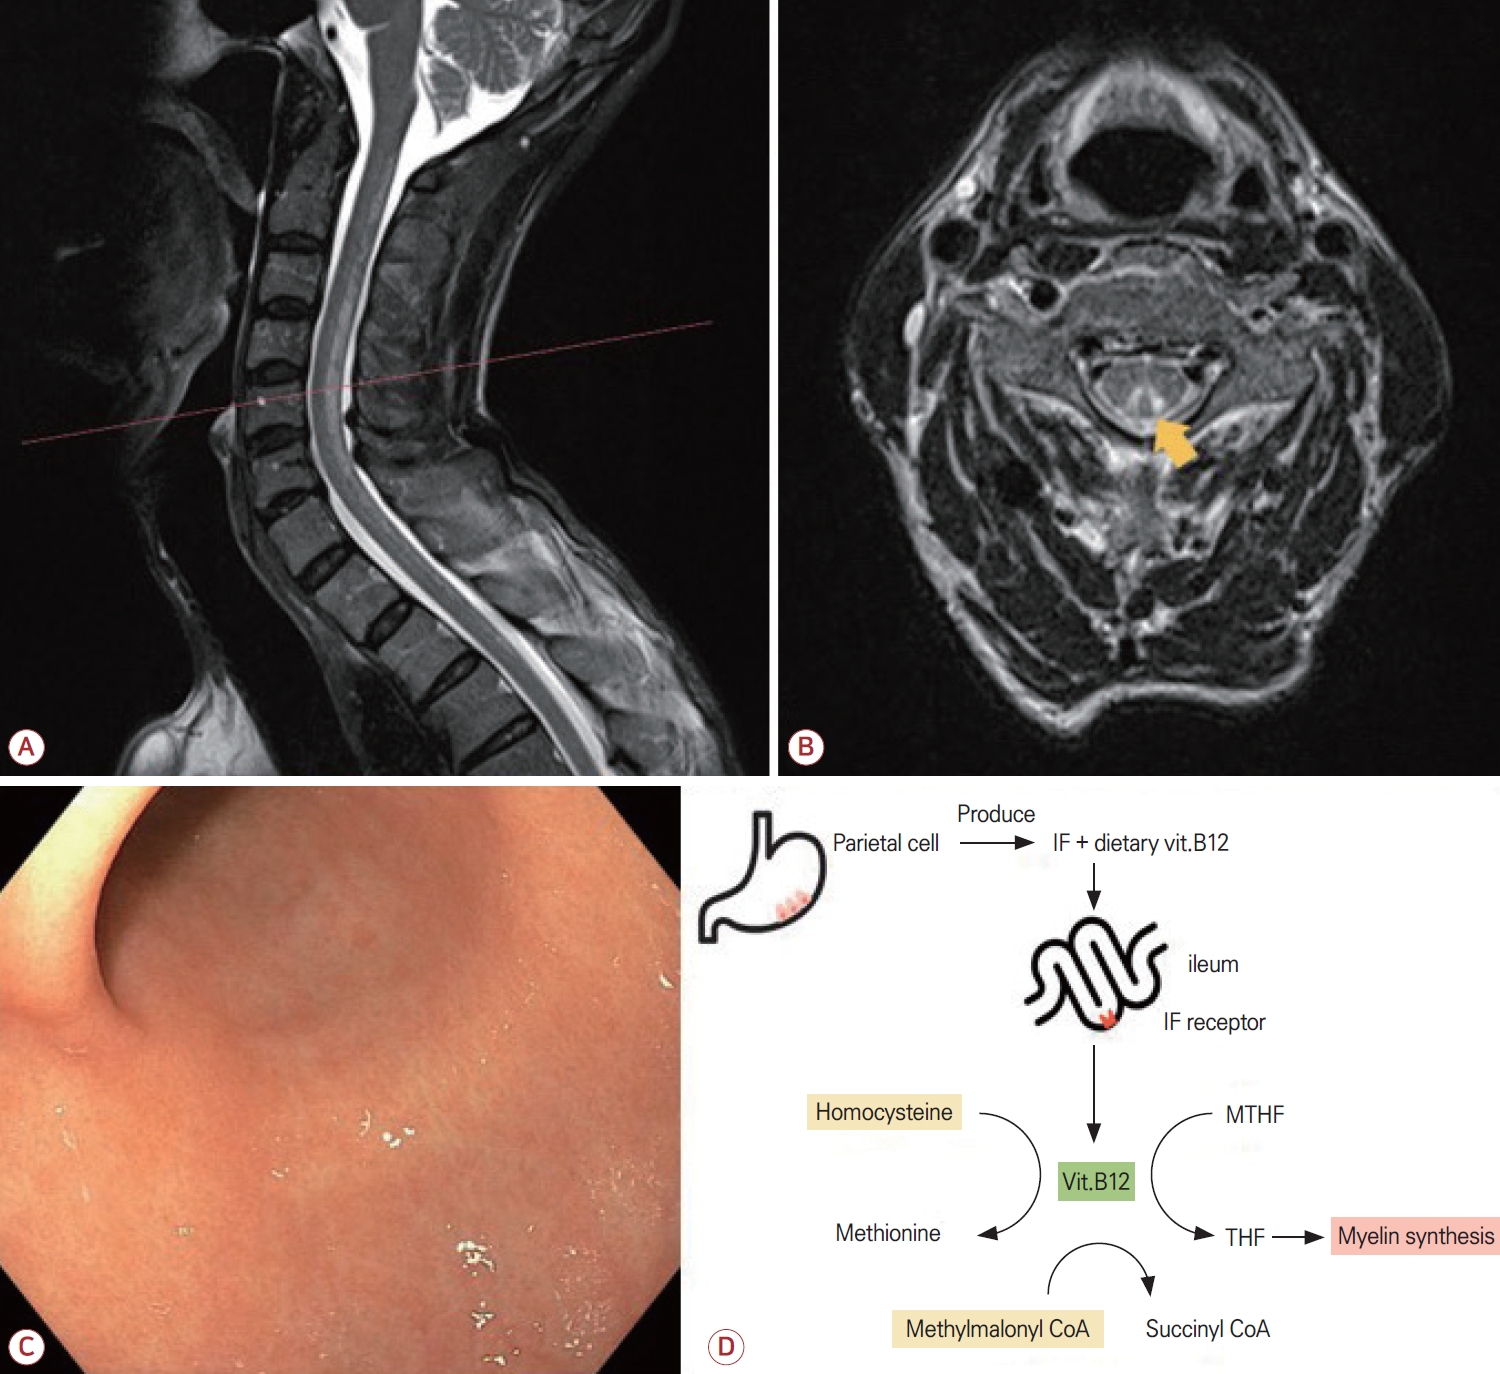

몸감각유발전위(somatosensory evoked potential, SSEP) 검사에서는 양측 정중신경(median nerve)의 중심전도로 지연이 확인되었고 양측 정강신경(tibial nerve)에서도 전도 이상이 의심되었다. 척수 자기공명영상(magnetic resonance imaging, MRI)에서는 경추 및 흉추의 뒤기둥에 고신호병터가 확인되었고(Fig. A) 가로횡단면에서 뒤집힌 V징후(inverted V sign)가 관찰되었다(Fig. B). 상부위장관내시경에서는 만성 위염 소견만 관찰되었으며(Fig. C) 조직 검사에서도 만성 위염이 확인되었다. 헬리코박터균(Helicobacter pylori)에 대한 중합효소사슬반응(polymerase chain reaction, PCR)은 음성이었고 혈청 가스트린(gastrin)은 575 pg/mL (정상, 13-115)로 상승되어 있었다. 위벽세포항체(anti-parietal cell antibodies)는 음성이었으나 내인자(intrinsic factor, IF)항체는 양성이었다. 위점막 생검에서는 모든 부위에서 만성 위축위염 소견이 보였고 위바닥(fundus)에서는 위오목증식(foveolar hyperplasia)이, 위몸통(mid body)에서는 위오목증식 및 장상피화생(intestinal metaplasia)이 추가적으로 관찰되었다. 소화기내과 협진을 통해 AIG가 고려된다는 답변을 받았으며 신경계 진찰과 영상 및 혈청 검사 소견을 종합하여 AIG로 인한 비타민B12 결핍에 의한 SCD로 진단하였다.

IF는 위의 벽세포에서 분비되는 당단백질로 회장에서 비타민 B12 흡수를 위한 필수적인 역할을 한다. 악성 빈혈에서는 IF 또는 벽세포에 대한 자가항체가 존재하여 비타민B12 흡수를 방해하고 이로 인하여 전신 결핍 상태로 이어진다. 비타민B12는 메싸이오닌 합성 및 수초 유지에 중요한 역할을 하며 결핍되면 메틸화장애, 메틸말론산 축적, 수초 손상이 유발되어 척수의 뒤기둥 및 가쪽기둥에 병터가 발생한다[12]. 이로 인하여 감각실조, 감각이상, 경직 등의 증상이 SCD로 나타난다(Fig. D).

(A) Sagittal T2-weighted MRI of the spine showing a longitudinal hyperintense signal predominantly involving the dorsal columns of cervical to upper thoracic cord levels. (B) Axial T2-weighted image at the level indicated in (A) demonstrating inverted V sign (arrow), a hallmark of subacute combined degeneration. (C) Upper gastrointestinal endoscopy showing mild diffuse erythema and mucosal granularity compatible with chronic gastritis, with no overt endoscopic atrophy. (D) Pathophysiological schema linking autoimmune gastritis to vitamin B12-related myelopathy. Gastric parietal cells produce intrinsic factor (IF), which binds dietary vitamin B12 and enables its uptake in the terminal ileum via the IF receptor. Absorbed B12 circulates on transcobalamin and serves as an essential cofactor for methionine synthase and for methylmalonyl-CoA mutase. In autoimmune gastritis, reduced IF-mediated absorption leads to cellular B12 deficiency, resulting in elevated homocysteine and methylmalonic acid and culminating in posterior column demyelination characteristic of subacute combined degeneration. vit.B12; vitamin B12, MTHF; methylenetetrahydrofolate, THF; tetrahydrofolate, MRI; magnetic resonance imaging.